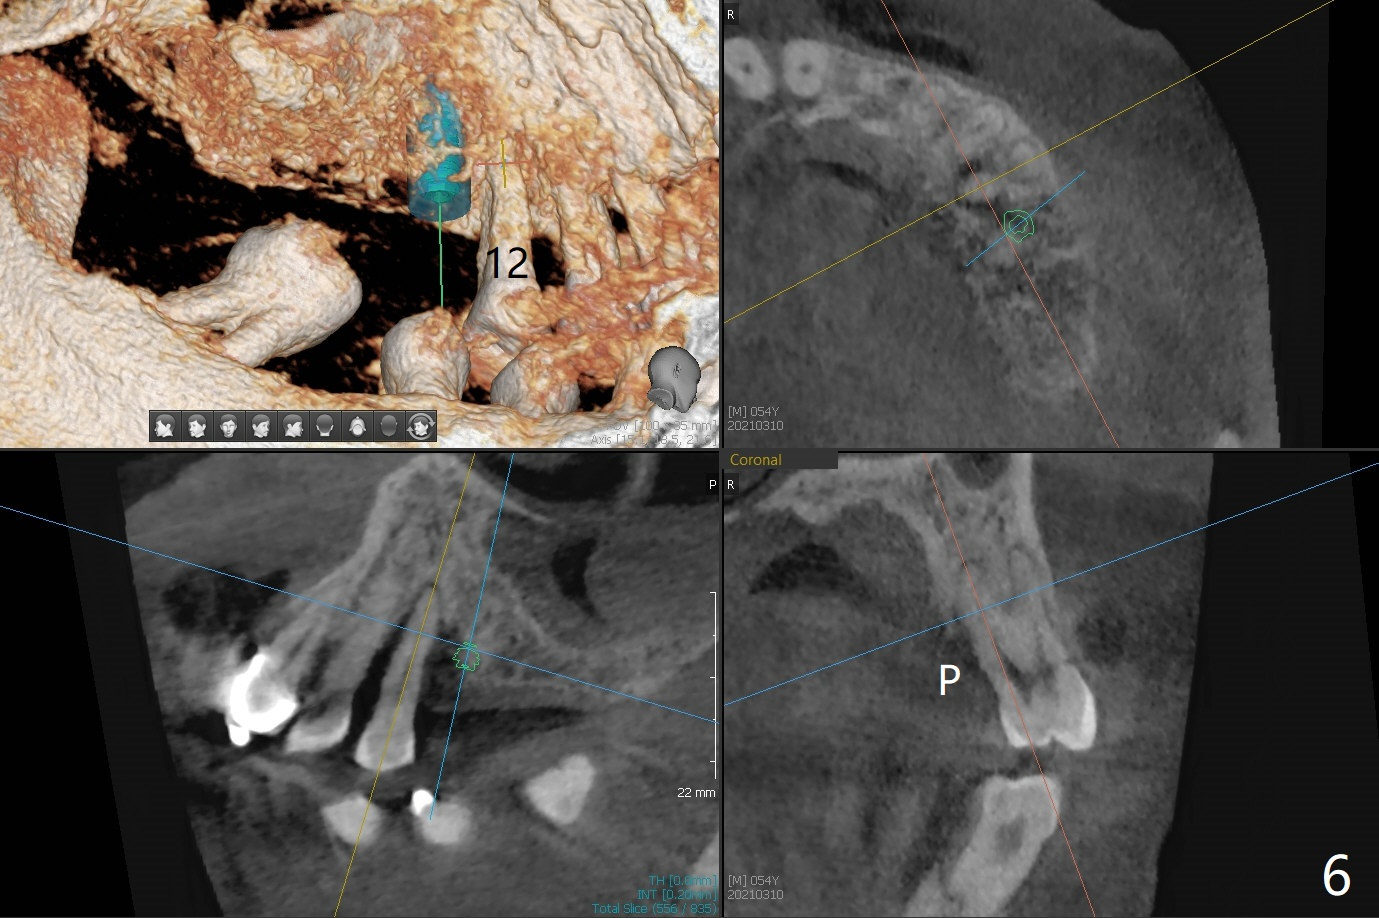

54岁男,28,29植骨后5个月,回来要求3,13,28,29种植(图一)。3号牙需要切开除去残根(图二:*),然后导板种植,准备两个PRF膜。为了保证植牙间距离,尝试在28,29处植入3.5x13毫米植体(图三,四)。在13号牙种植时(图五),考虑12号牙腭侧植骨(图六)。为了减少对12号牙咬合创伤,考虑4个植牙即刻修复。